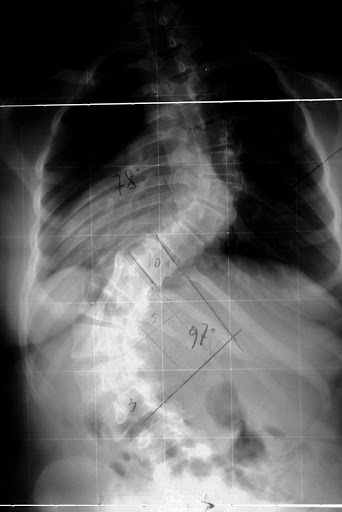

Il grado di curvatura oltre il quale si considera la comparsa della patologia è 10° Cobb, in questi casi è quasi sempre asintomatica. Nell'età aduta invece si considerano 30° gradi Cobb quelli in cui c'è l'esordio della sontomatologia dolorosa, e 50° Cobb sono invece la soglia di tenuta strutturale della colonna, oltre i quali c'è indicazione al trattamento chirurgico, indicato anche per prevenire complicanze organiche a livello polmonare e cardiaco.

L'esame strumentale per eccellenza è la radiografia che viene fatta in toto sul rachide, in 2 proiezioni anteriore e laterale (a meno che non si supponga qualche altra patologia che indurrà a fare degli scatti anche in altre proiezioni). Si effettua una rx anche in posizione supina per escludere gli effetti della forza di gravità silla curva scoliotica.

L'interpretazione delle radiografie permette di classificare la scoliosi in base ai gradi di deviazione (Cobb) ed in base alla chiusura o meno dei nuclei di ossificazione delle cartilagini (Risser).

Dalle radiografie innanzitutto si può capire se trattasi di scoliosi vera (rotazione delle spinose vertebrali attorno all'asse longitudinale) oppure di una deviazione che laterale senza rotazione delle sponose.